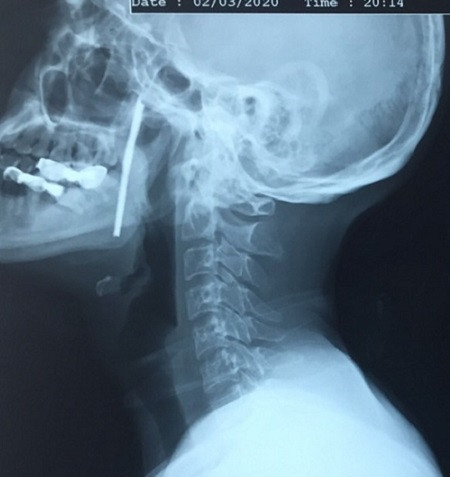

Bị thanh sắt nhọn bắn xuyên cổ, người đàn ông may mắn được cứu sống ảnh 1Hình ảnh chụp phim cho thấy thanh sắt nhọn xuyên từ cổ lên vùng miệng dài 10 cm

TS Vũ Ngọc Tú, Trung tâm Phẫu thuật Tim mạch và Lồng ngực - Bệnh viện Việt Đức cho biết, người bệnh được chẩn đoán vết thương phức tạp vùng cổ, do dị vật kim loại dài,  xiên từ hầu họng vào trong miệng.

Đây là vùng có rất nhiều cơ quan hệ trọng của cơ thể như đường thở (khí quản), đường ăn (thực quản), các mạch máu nuôi não (động mạch cảnh)... Rất may mắn là thanh sắt chưa trực tiếp gây tổn thương các thành phần này, nhưng lại nằm sát cạnh tất cả các cấu trúc đó nên gây khó khăn lớn khi phẫu thuật.

Sau khi tính toán kỹ càng, đề phòng mọi biến chứng có thể xảy ra và cân não suốt quá trình phẫu thuật, người bệnh đã được các bác sĩ phẫu thuật cấp cứu thành công. Dị vật kim loại đã được lấy ra dài hơn 10cm, rất sắc nhọn.